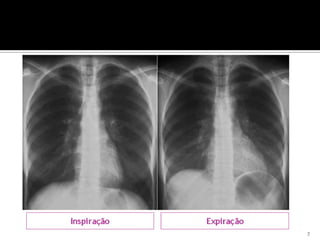

O documento discute o sistema respiratório humano, incluindo sua constituição, ventilação pulmonar, processos de inspiração e expiração, trocas gasosas e hematose pulmonar, e doenças e atitudes preventivas do sistema respiratório.